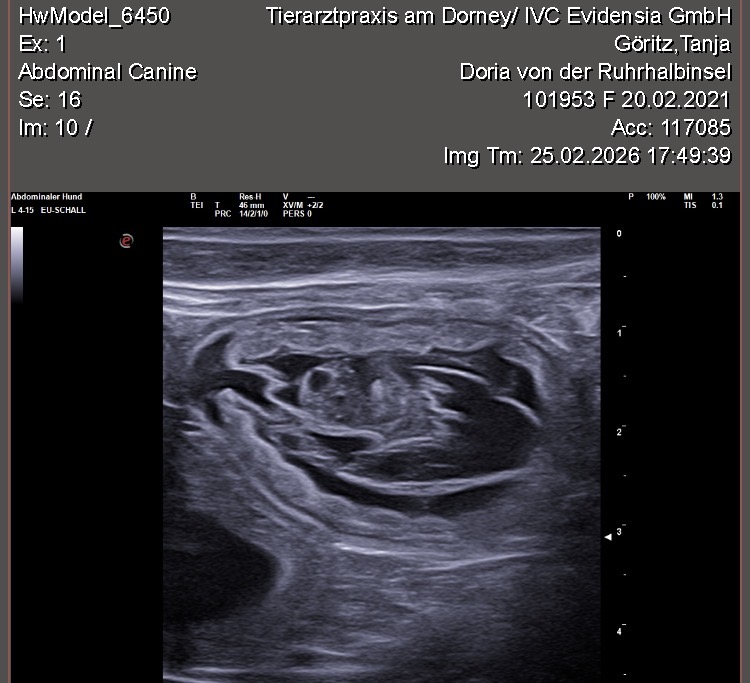

Wir waren erfolgreich und konnten Fruchtanlagen mit schlagenden Herzen sehen. Wir gehen zum aktuellen Zeitpunkt wieder von einem größeren Wurf aus. Daykos und Dorias Rendevouz war also sehr vielversprechend!

Hier zeigen wir euch einige der kleinen gefüllten Fruchtblasen mit Inhalt und schlagenden Herzen. Da wir kurz vor Ostern mit der Geburt rechnen, nennen wir sie „Ostereier“ 🙂